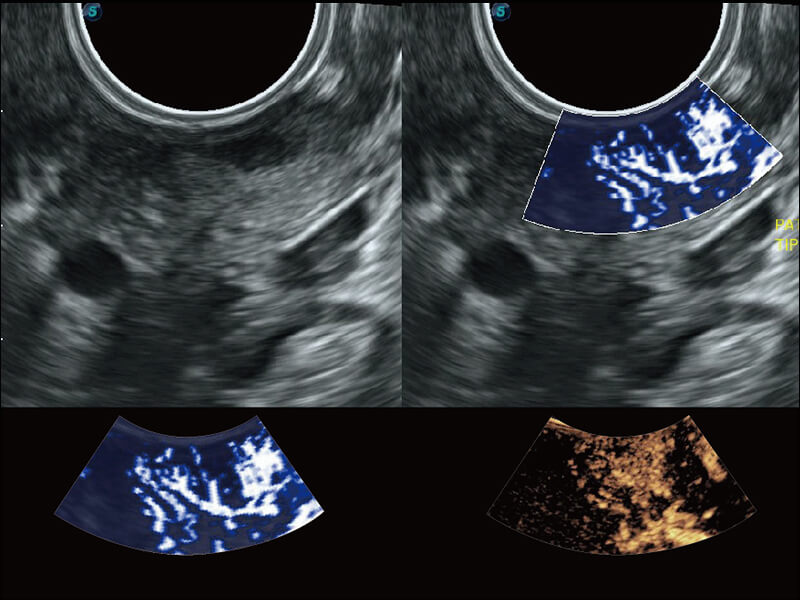

成像功能

性能优异的硬件架构,极大提升超声系统的运行效率和数据处理能力。相比以往超声成像系统,Wis+平台为您带来极快的响应速度和成像帧频,提升检查流畅度。

S60探头工艺,从前端信号处理每一个环节采集无损声学数据,真实还原组织原貌,再现解剖细节。